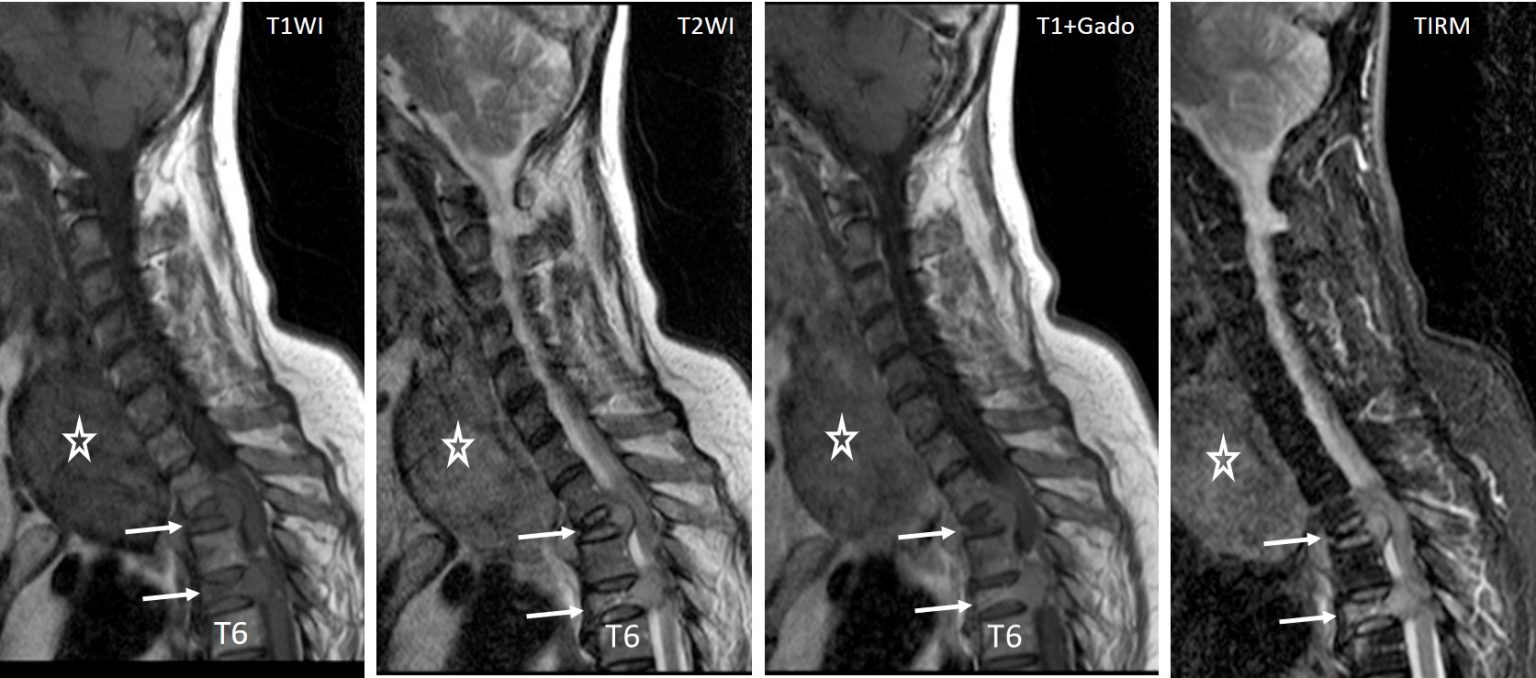

From www.researchgate.net

Preoperative thoracic spinal MRI shows compression fractures of T7 Compression Fracture Mri With Or Without Contrast Compare the reasons, procedures, and. Find out how to distinguish between osteoporotic and pathological. Learn about the causes, types, classification, diagnosis and treatment of spinal compression fractures on radiographs. These suggestions are general guidelines that apply to the use of contrast for mri exams provided at oregon imaging centers. On conventional imaging, acute fracture signs include cortical breaking or impaction. Compression Fracture Mri With Or Without Contrast.

MRI on 1st admission. Recent benign compression fracture of T10 body Compression Fracture Mri With Or Without Contrast Find out how to distinguish between osteoporotic and pathological. These suggestions are general guidelines that apply to the use of contrast for mri exams provided at oregon imaging centers. Learn about the causes, types, classification, diagnosis and treatment of spinal compression fractures on radiographs. Learn about the causes, symptoms, complications, and treatment options for vertebral compression fractures (vcfs), the most. Compression Fracture Mri With Or Without Contrast.